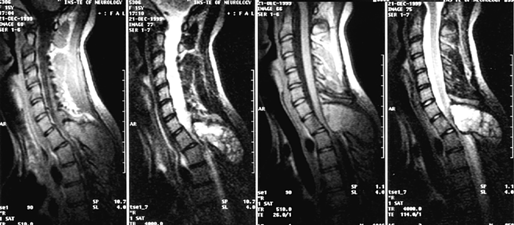

Диагноз уточняется с помощью МРТ, введение контрастного вещества улучшает визуализацию границ опухоли (рис. 1), хотя окончательно наличие четкой границы со структурами спинного мозга и, соответственно, возможность радикального удаления опухоли устанавливаются только в ходе операции.

Рисунок 1. Интрамедуллярная опухоль (астроцитома) шейного отдела спинного мозга (МРТ с контрастным усилением, Т1-взвешенные изображения)